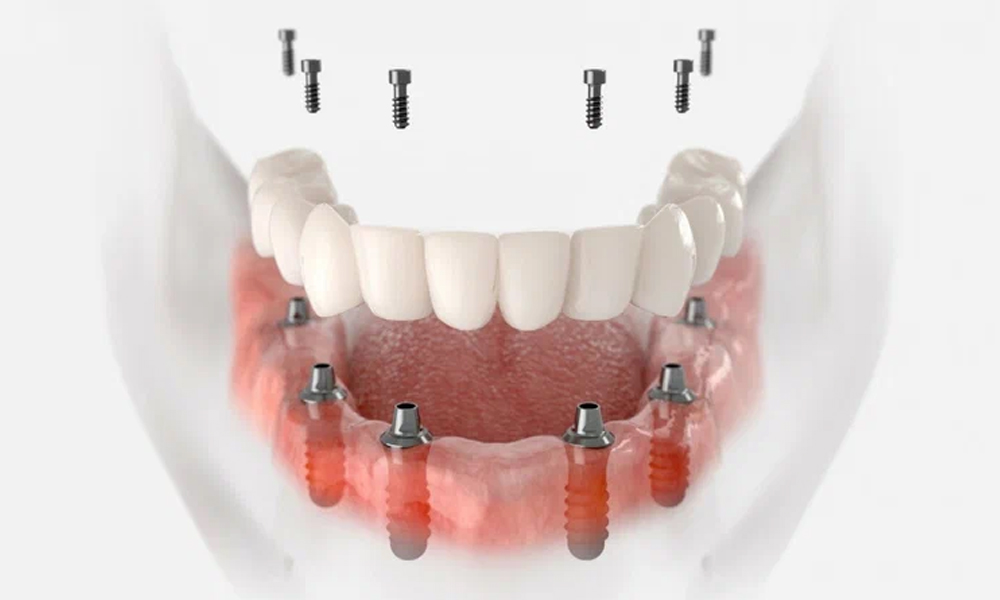

ایمپلنت تمامفک (All-on-4 و All-on-6) | جایگزین کل دندانهای فک با استفاده از ۴ تا ۶ پایه ایمپلنت؛ بازسازی سریع و اقتصادی. |